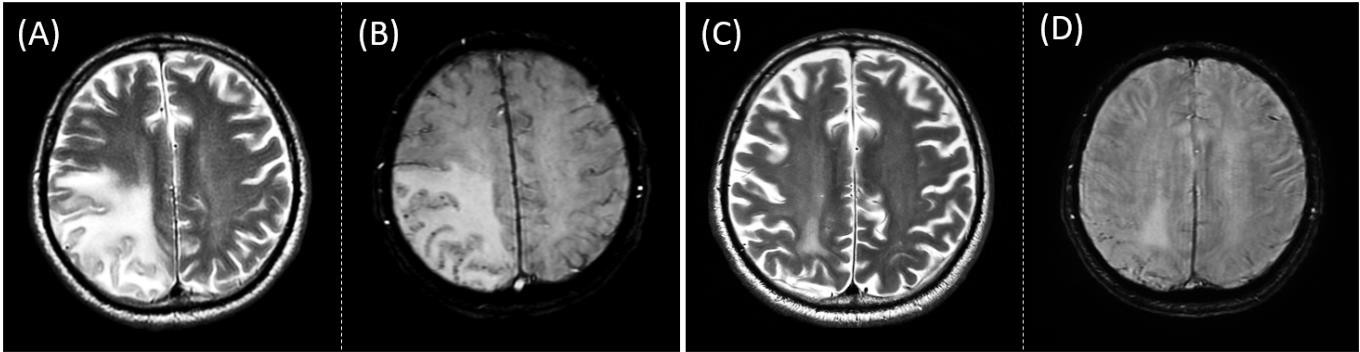

3. ábra. Remisszióban lévő CAA-RI betegeink egy reprezentatív esete. (A) Néhány nap leforgása alatt kialakult súlyos jobb agyféltekei tünettan, hallucinációk és epilepsziás rosszullét hátterében kiterjedt T2 jelintenzív agyödéma igazolódott. (B) A vérzésre érzékeny szekvencián az ödéma és a felette lévő agykéregrészekben észlelhető számos, mikrovérzésnek megfelelő pontszerű apró jelszegény (fekete) eltérés együttesen CAA-RI-re utal. (C) Nagy dózisú vénás szteroid kezelés után 2 hónappal a beteg neurológiai és kognitív állapotának teljes helyreállását a T2 jelintenzív ödéma csaknem teljes eltűnése kísérte. (D) A vérzéses eltérések száma nem nőtt tovább. (Két évvel később már az ödéma maradéka sem volt látható, az antiepileptikum is leállt.)

Szalardy et al. 2024, Neuropathology and Applied Neurobiology nyomán